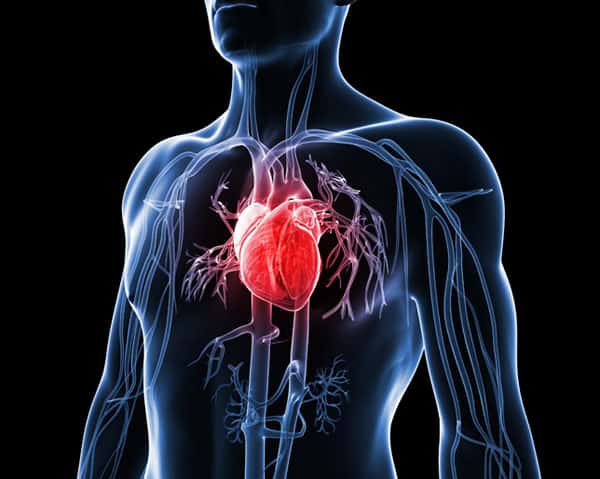

Just like any muscle, if you don’t exercise them and make them work they’ll steadily become weaker. We know that as people get older, if they don’t ‘use’ their cardiovascular system, it gets weaker, and because of this, prone to developing disease.

The harder and more frequent your heart beats, the sharper it stays.

Lots of people don’t take as much care of their body as they should. They eat foods with too much refined sugar, salt and fat that enters the blood and damages the blood vessels from the inside. This happens all over the body, but because the heart is so important it often causes chest pain symptoms.

The heart is the only muscle that contracts about once a second from before you’re even born, to the day you die. That’s more than 2.5 trillion times in a typical person